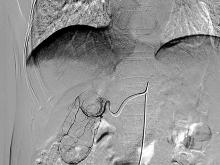

口服膽囊造影正常膽囊於服藥後12-15h顯影較好,密度均勻。膽囊常為茄形或梨形緻密影,長7-10cm,寬約3-4cm,位於右上腹肝下緣下方。

口服膽囊造影的具體方法是:造影前一日行腹部透視,注意膽囊區有無鈣化及膽道充氣。一般可用緩瀉藥,以排除積氣。造影前一日下午進脂肪晚餐後約1小時服藥。可用碘番酸或碘阿芬酸,每劑6片(每片0.5g,共3g),可每隔5分鐘服1片,服完3g,然後除少量飲水外,不再進食。翌日在服藥後13~14小時攝片,如膽囊已顯影,可進油煎雞蛋3個,30~40分鐘後再攝片,可觀察膽囊的收縮情況。正常情況下,膽囊可縮小到原來體積的1/3~1/2。如膽囊收縮不滿意,可推遲到60分鐘時再拍1張。如在1次服碘番酸後膽囊不顯影,可在拍片當天晚上再服6片(即雙倍劑量),翌日再拍片或隔2周后,服雙劑量後再拍片。